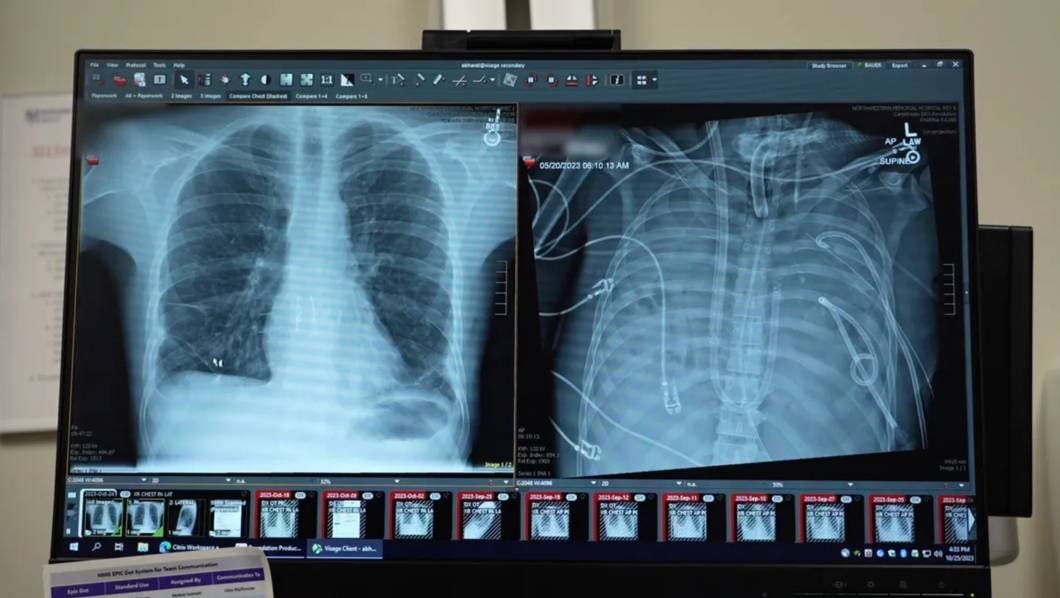

El hombre, de 33 años, llegó al hospital con un síndrome de distrés respiratorio agudo provocado por una infección grave que había causado daño irreversible en ambos pulmones. Ante la falta de opciones, un equipo de cirujanos de la Universidad Northwestern, liderado por el Dr. Ankit Bharat, decidió retirar los pulmones dañados y conectar al paciente a un dispositivo que oxigenaba su sangre y mantenía estable la circulación, en lo que se ha descrito como un verdadero puente vital hacia la cirugía de trasplante.

Más allá de su impresionante supervivencia, el caso representa un hito científico: es una de las primeras veces que se demuestra que un sistema artificial puede reemplazar temporalmente por completo la función pulmonar humana mientras se espera un donante compatible. El análisis molecular de los pulmones extraídos reveló que el daño era tan severo que no podría haberse recuperado por sí solo sin un trasplante — algo que aporta datos valiosos para futuras terapias en casos de falla pulmonar aguda.